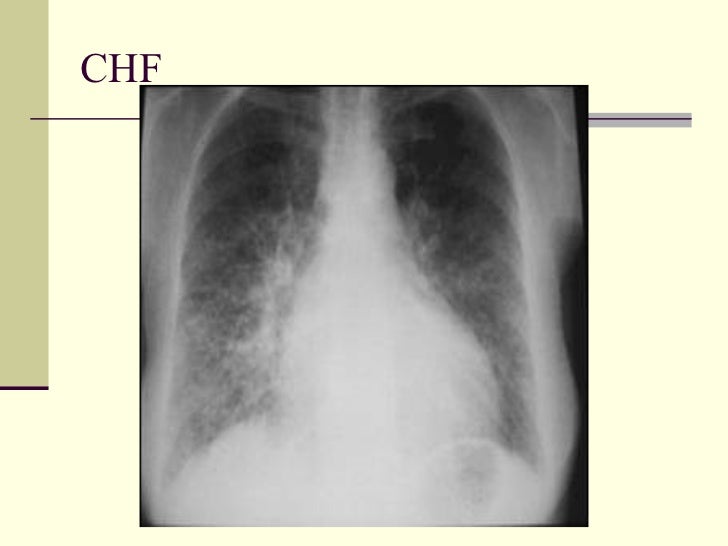

54. 62. CHF

53. 61. <ul><li>Pulmonary Interstitial Edema </li></ul><ul><li>1. CHF </li></ul><ul><li>2. Lymphangitic spread </li></ul><ul><li>3. Allergic reaction </li></ul>